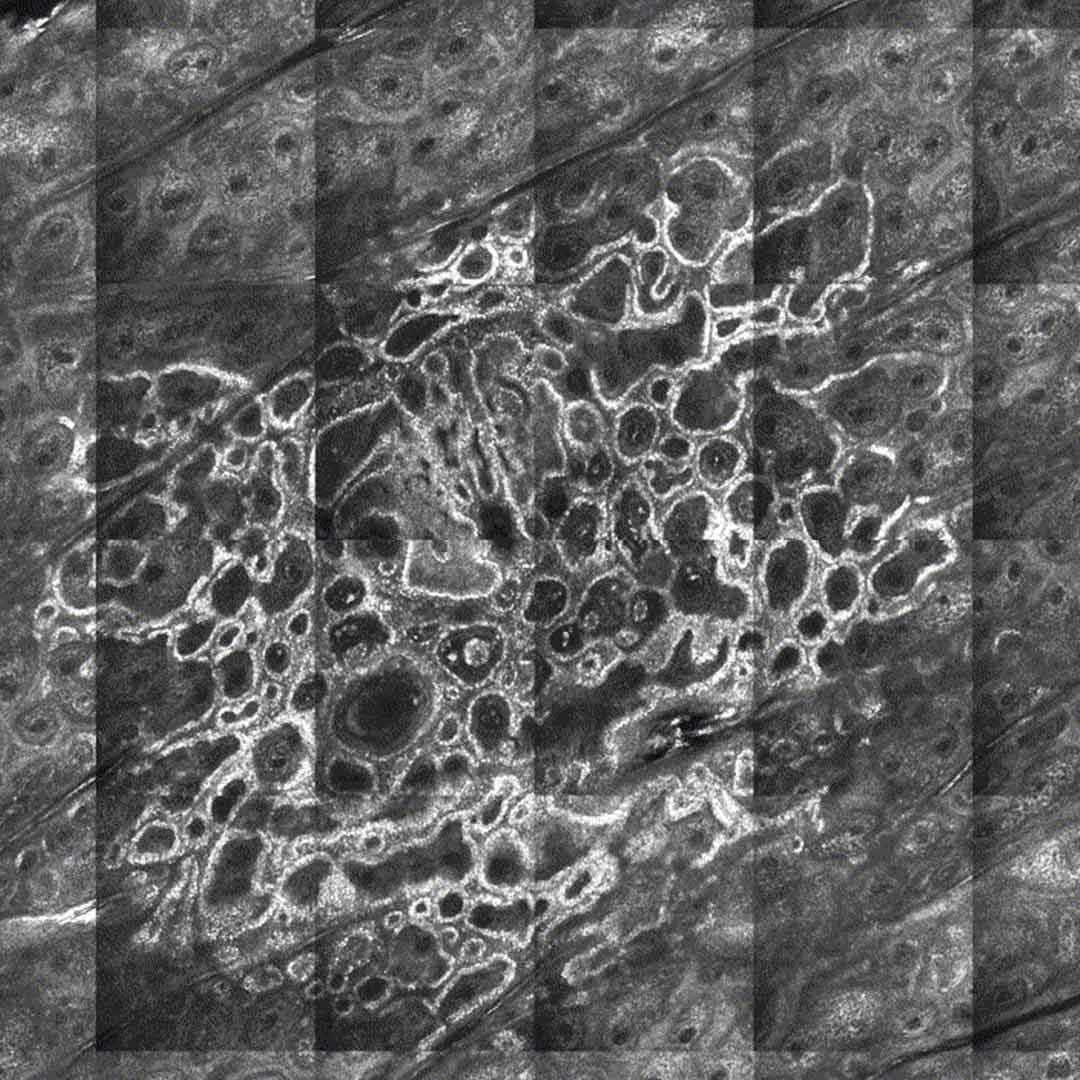

Die Auswertung der konfokalen Aufnahmen wird von Frau Dr. med. Andrea Zorn durchgeführt. Sie ist auf diesem Gebiet eine der wenigen sehr erfahrenen Expertinnen, die sowohl über das entsprechende Fachwissen wie auch über die nötige Erfahrung verfügt. Bei der Auswertung geht es darum kleine Unregelmäßigkeiten in den Hautzellen zu erkennen und dabei bösartige Veränderungen, von normalem Gewebeteilen und gutartigen Abweichungen zu unterscheiden. Anhand einiger Beispielaufnahmen können Sie selber sehen, welche hohe Konzentration und welches hohe optische Vorstellungsvermögen vom Arzt erwartet wird, um selbst die kleinsten Merkmale zu erkennen.

Die Auswertung der 3-Dimensionalen Aufnahmen (Laserscans) erfordert vom Arzt ein sehr hohes optisches Vorstellungsvermögen und das entsprechende Wissen, wie sich krankhafte Hautzellen im Vorstadium strukturell von anderen unterscheiden. In diesem noch recht jungen und sehr spezialisierten Forschungsbereich ist die 1175 gegründete Universität Modena (Università degli Studi di Modena e Reggio nell’Emilia) europaweit führend. Dort hat Frau Dr. Zorn spezielle Kurse bei Prof. Dr. med. Pellacani besucht und die Prüfungen mit Erfolg abgelegt. Außerdem ist sie Mitglied im Arbeitskreis der konfokalen Lasermikroskopie, um über aktuelle Entwicklungen auf dem neusten Stand zu bleiben. Insgesamt kann für die Ausbildung zeitlich ein gutes Semester veranschlagt werden.

Ein konfokales Lasermikroskop (auch laser scanning microscope oder Konfokalmikroskop) funktioniert so, dass ein Laserstrahl die zu untersuchenden Areale einzeln, aber mit gleichem (con-) Fokus, abrastert und die vielen einzelnen, sehr kontrastreichen Bildchen zu einem großen Bild zusammensetzt. So kann der Laser auch verschiedene über- und untereinanderliegende Ebenen der Haut abrastern und tiefer gelegene Hautzellen sichtbar machen. Dabei wird das vom Laser reflektierte Licht digital aufgenommen und zu einem 3-D Bild ergänzt. Dieses 3-dimensionale Bild steht dann zur Auswertung zur Verfügung. Weitere Informationen finden Sie bei Wikipedia oder dem Hersteller Vivascope.